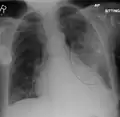

Left upper lobe pneumonia with a small pleural effusion.

The discovery of x-rays made it possible to determine the anatomic type of pneumonia without direct examination of the lungs at autopsy and led to the development of a radiological classification. Early investigators distinguished between typical lobar pneumonia and atypical (e.g. Chlamydophila) or viral pneumonia using the location, distribution, and appearance of the opacities they saw on chest x-rays. Certain x-ray findings can be used to help predict the course of illness, although it is not possible to clearly determine the microbiologic cause of a pneumonia with x-rays alone.

AP CXR showing left lower lobe pneumonia associated with a small left sided pleural effusion -